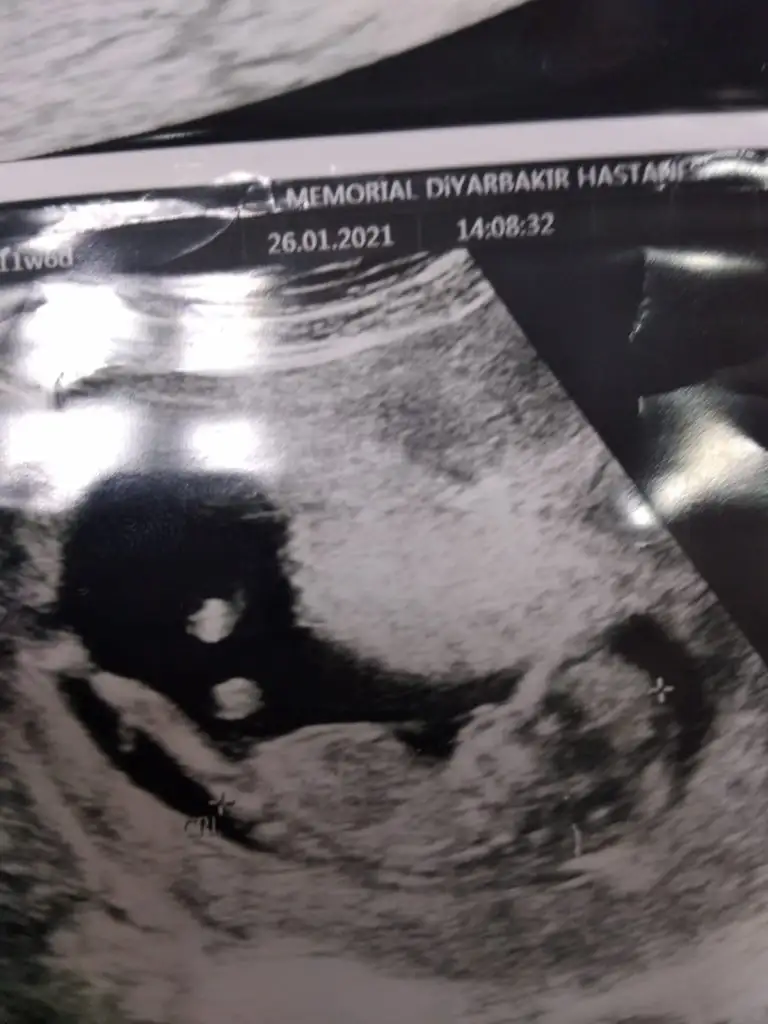

dün 2 li tarama testine girdim bebeğim uyuyordu doktor cinsiyet tahmini yapmadı renkli ultrasonografi görüntülerim var, bu resimlere göre cinsiyet tahmini yapabilirmsiiniz , bu ikinci gebeliğim 8,5 yaşında bir kızım var

mesajım görünmüyor mu acaba cevap alamadım, 12+5 de 2 li tarama yaptırdım, cinsiyet tahmini yapmadılar, bu görüntüler üzerinden tahmin yapabilirmisiniz